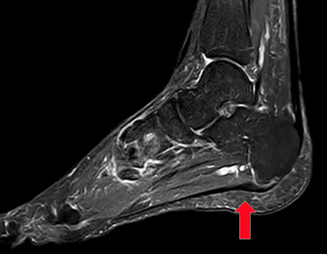

▶影像学检查可确诊,包括X光检查、超声和核磁共振。

图6:核磁共振示跖腱膜在跟骨结节处可见明显增厚(红色箭头)